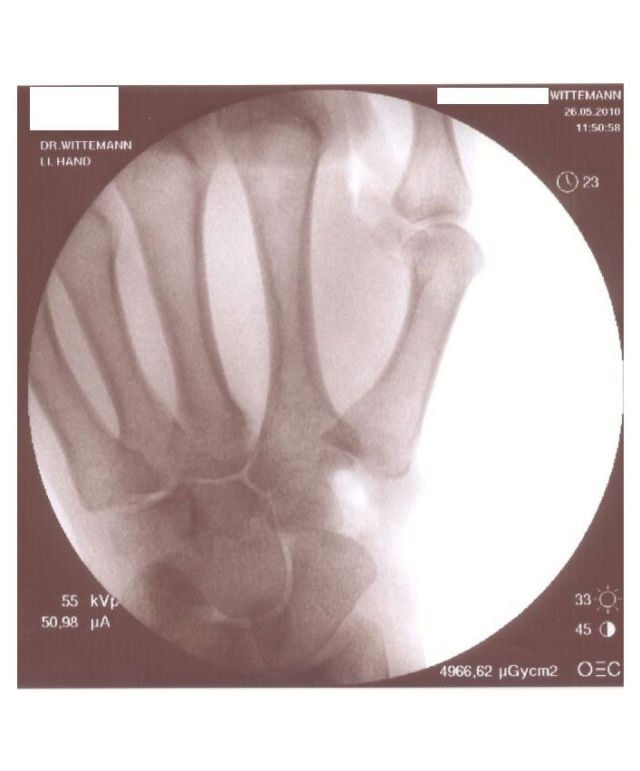

Sollte das Sattelgelenk so stark geschädigt sein, dass weder eine arthroskopische Gelenktoilette noch eine Korrekturosteotomie erfolgversprechend sind, so stellt die sogenannte „Resektionssuspensionsarthroplastik" seit mehreren Jahrzehnten den Goldstandard der operativen Behandlung der Sattelgelenksarthrose dar.

Bei diesem Eingriff wird das große Vieleckbein vollständig entfernt und eine direkt darunter liegende Sehne als Ersatz in die entstandene Lücke zwischen dem Kahnbein und dem 1. Mittelhandknochen gezogen, es gibt hierfür verschiedene Technik, wir verwenden eine sogenannte „Fadensuspension".

Postoperatives Röntgen nach Entfernung des Os trapezium